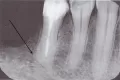

К сожалению, по вашему рассказу поставить точный диагноз невозможно. Это точно не герпес и не пародонтит, симптомы говорят, скорее всего, о хроническом воспалении на верхушках зуба или зубов. Для точного диагноза необходим очный приём доктора и рентген анализ. Рекомендую не тянуть и обратиться к врачу.